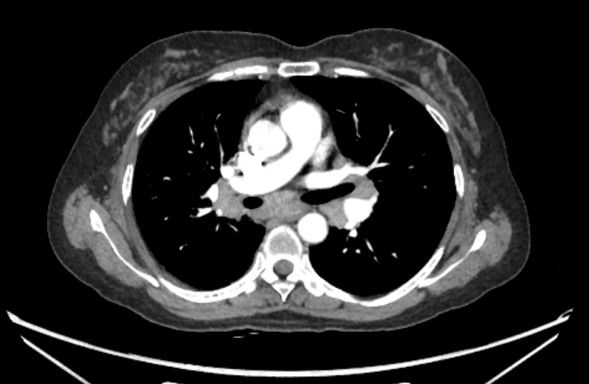

胸部CT:纵膈淋巴结肿大 双肺多发粟粒结节影

7组淋巴结肿大

4R组淋巴结肿大